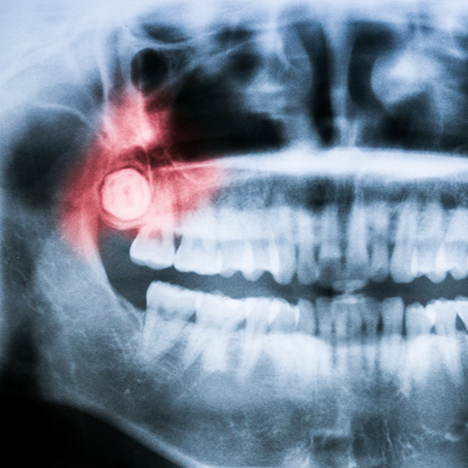

During an initial examination, we will take X-rays to determine the exact location and state of your wisdom teeth. If extraction would benefit your oral health, we can schedule the procedure. We offer plenty of sedation options to ensure your comfort.

Once your mouth is numb and you’re completely comfortable, we make a small incision in the gum tissue surrounding the wisdom tooth. After removing it, we suture the site to minimize bleeding. You’ll likely experience some swelling and discomfort for the next few days. Carefully follow our post-op instructions, which often include sticking to a soft food diet and giving yourself plenty of time to rest.